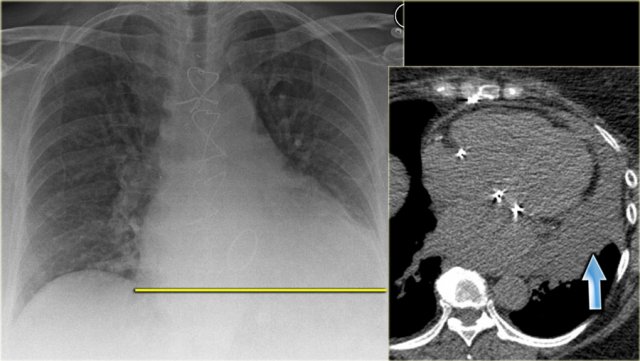

On the left a patient who was admitted with severe dyspnoe due to acute heart failure.

The following signs indicate heart failure: alveolar edema with perihilar consolidations and air bronchograms (yellow arrows); pleural fluid (blue arrow); prominent azygos vein and increased width of the vascular pedicle (red arrow) and an enlarged cardiac silhouette (arrow heads).

After treatment we can still see an enlarged cardiac silhouette, pleural fluid and redistribution of the pulmonary blood flow, but the edema has resolved.